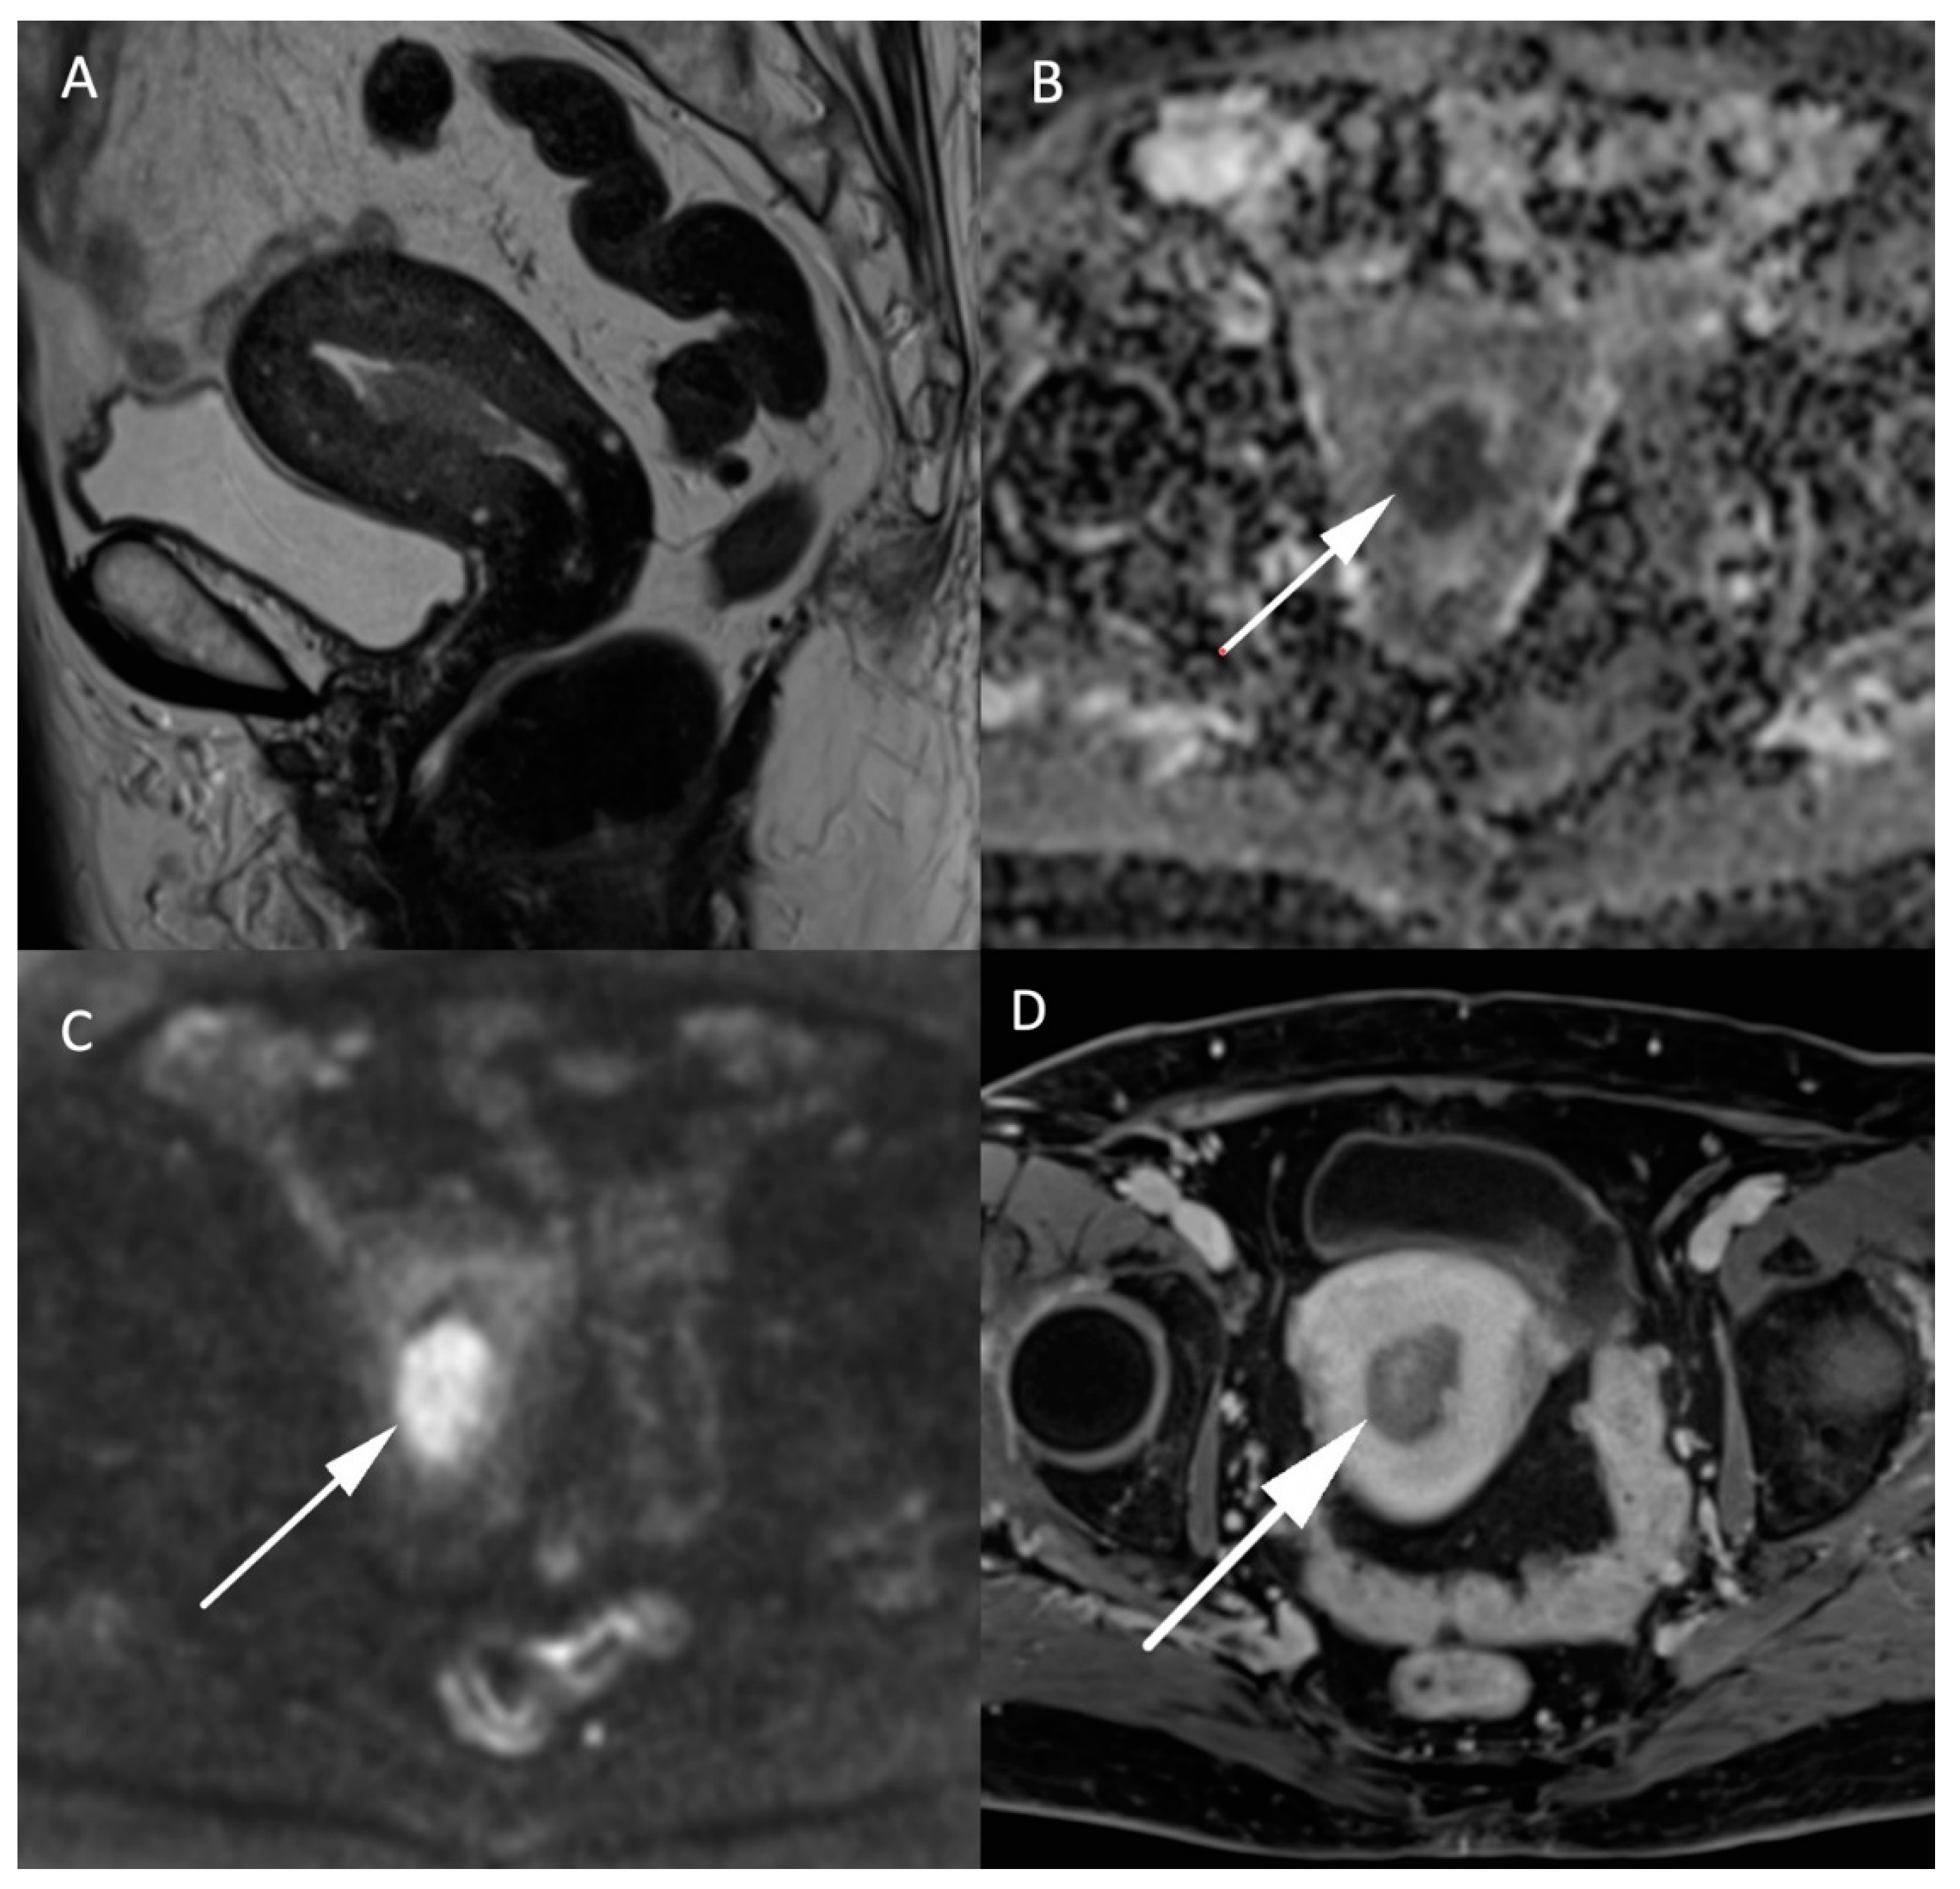

MRI in endometrial cancer is performed for the staging of the disease. Invasion of less than 50% of the myometrium to separate stage Ia and Ib is based on a morphologic T2W plane perpendicular to the endometrial cavity. Endometrial cancer is usually hyperintense to the myometrium but can be difficult to differentiate from the surrounding tissue as illustrated in Figure 3. On DWI cancer shows diffusion restriction with a high b-1000 signal and low ADC values compared to the normal endometrium and adjacent myometrium. The addition of DWI to T2W imaging significantly improves the staging of endometrial cancer [26,27]. It is even more indispensable in patients with impaired renal function who cannot benefit from gadolinium administration, and therefore, from contrast-enhanced MRI. However, the combination of DWI and contrast-enhanced MRI remains the best approach to predict myometrial invasion, as supported by a recent study on machine learning [28]. DWI is also helpful in detecting other pelvic depositions in high grade tumors [8]. A false positive high signal on DWI with low ADC values in the endometrial cavity corresponds to secretory and hyperplastic endometrium or blood during the female cycle which is easily recognized by its high signal on T1W FatSat sequences [8].

Figure 3.

MR images of an endometrial carcinoma in a 93-year-old woman. (A) Sagittal T2W image in the endometrial cavity with extension in the myometrium smaller than 50% of its thickness. (B) ADC map shows a restricted diffusion in the endometrial carcinoma visible as a “dark” area (arrow) in opposition with (C) high signal (arrow) on high b-value images (b = 1000 s/mm2). (D) post injection of gadolinium T1W image shows the endometrial carcinoma (arrow) with an enhancement less than the myometrium’s muscle.